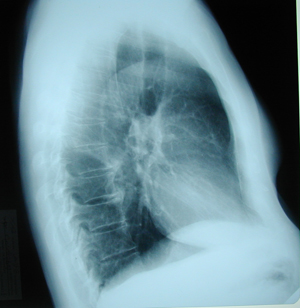

Εικόνα 2

Πλάγια ακτινογραφία θώρακος. Διακρίνεται μάζα στον άνω λοβό στο ύψος του αορτικού τόξου.